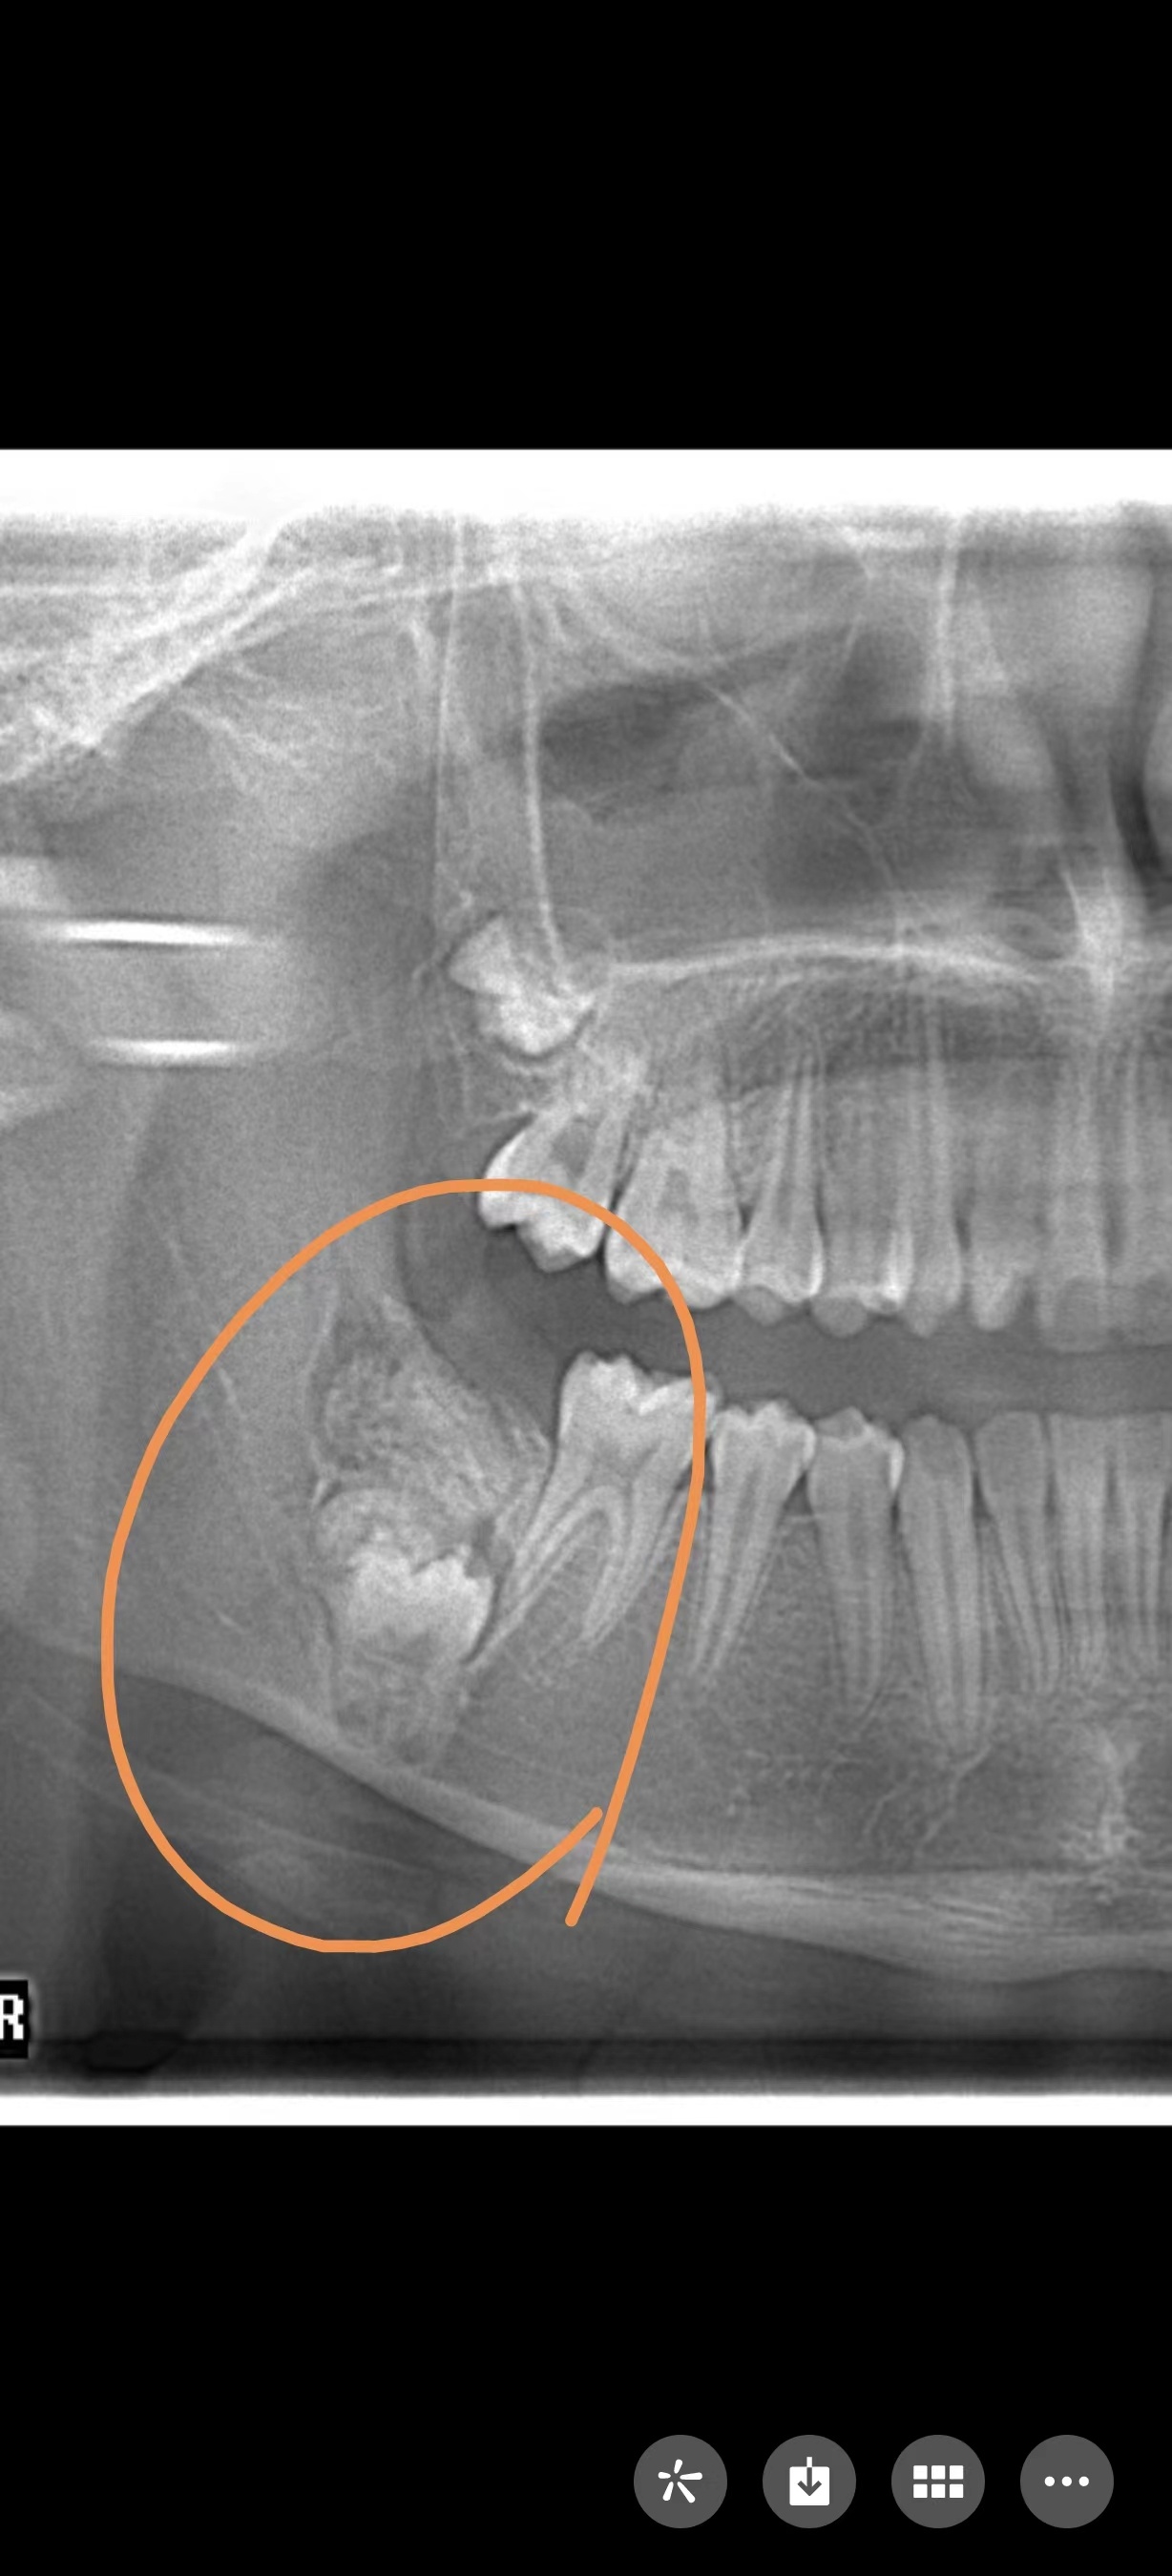

近日,12岁的小雅因为牙齿不齐前来上海市儿童医院口腔科做正畸治疗,拍片发现小雅的右下颌骨内发生了瘤样病变,因此导致其右下第2恒磨牙在顶出来的途中遇到“埋伏”,无法正常长出。

口腔科主治医师段阿竹告诉记者,牙瘤是牙源性肿瘤中的一种,生长于颌骨内,是以牙体组织杂乱排列成团或形成数量不等的畸形牙为特征的牙的发育畸形,并非真性肿瘤,瘤体内可含有不同发育阶段的各种牙胚组织或牙,数个至数十个不等,形状不规则,有的近似正常牙,有的只是一团紊乱的硬组织,周围包裹着一层纤维膜。

牙瘤病因较复杂,多种因素均可能与牙瘤的发生相关,如乳牙的慢性炎症和感染遗传因素、成牙本质细胞过度反应等,均可能导致牙瘤发生,牙瘤患者常有缺牙现象,牙瘤可引起恒牙迟萌、疼痛、颌骨膨隆、邻牙移位、松动,病变范围较大,可导致骨缺损甚至引起骨折。

牙瘤手术的实施难度与瘤体生长的位置有关,如果牙瘤处于颌骨内,需要在右下颌后牙区开展手术,术野范围局限以及埋伏恒牙临近下牙槽神经区域,会增加了手术难度和术中风险。

小雅的牙瘤就生长在颌骨内,手术难度较大,但在手术中,口腔科团队使用了最新的超声骨刀微创去骨法,尽量保留正常的颌骨组织,最大程度保护粘膜组织及正常的恒牙。而且手术在全麻下进行,医生在足够空间视野下操作,减少了手术时长,最大限度地减轻了患儿心理和身体上的恐惧和疼痛。